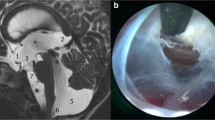

There was no significant difference observed in the preoperative and immediate postoperative Heidelberg score changes between the success and failure groups (p-value of 0.433 and 0.555). However, a highly significant difference (p = 0.002) was observed in the Heidelberg score at 3 months in the success group (SG) compared to the failure group (FG). Additionally, at one-year, a significant difference was observed in the SG and the MRI at the time of failure in the FG (p < 0.001). For a summary of the results, please refer to Table 2, while examples of success and failure score values are shown in Figs. 4 and 5, respectively.

Pre-, 3-months and failure mid-sagittal CISS* magnetic resonance images of a 2 years old patient, who showed a preoperative Heidelberg score of + 2 (TVF** + 1 and LT*** + 1) (A), postoperatively 3 months later, the Heidelberg score went to -1 (TVF -1 and LT 0) (B), after 9 months, the patient showed hydrocephalic symptoms again and the Heidelberg score increased to + 2 (TVF + 1 and LT + 1) (C). 1 year after Re-ETV score dropped back to -1 (TVF -1 and LT 0) (D). *Constructive interference in steady state ** Third ventricle floor ***Lamina terminals